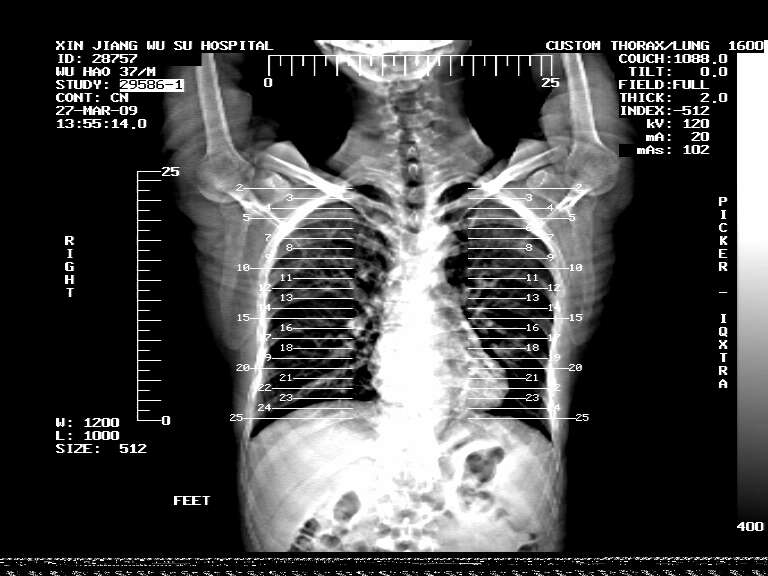

标题: CT19113:体检胸透发现阴影,CT图像。

男,37岁,体检胸透发现阴影。

患者体检发现 无症状 左肺下叶占位,边缘模糊,可见血管聚束、分叶、胸膜牵拉,增强呈不均匀性强化。 首先考虑左肺下叶周围型肺癌,建议穿刺活检。

左肺下叶见一结节病变,边缘欠清不光滑,与胸膜粘连且胸膜局限性增厚,注药后呈环形强化,动脉期壁呈明显点环状强化,静脉期壁强化减低,中心密度低无强化,灶周无明显的卫星灶和水肿区(晕征)---考虑周围性肺癌,不除外感染性病变,建议穿刺活检。

左肺下叶软组织病灶,密度较高,内见点状钙化,其周围见子灶,邻近胸膜扁平样增厚.c+病灶强化明显,中心强化弱.诊断:左肺下叶结核瘤.

左肺下叶大片实变影,内靠胸膜见不规则更高密度结节灶,边缘强化,相邻胸膜增厚,胸膜下脂肪线存在。考虑炎症,结核可能。